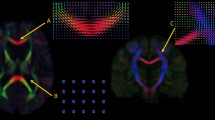

Microsaccade dynamics between LLD and CTRL. (A) Dynamics of microsaccade rates following background luminance changes between LLD and CTRL, and mean rates (− 700 to 1700 ms) for each group. (B) Microsaccade main sequence, intercept, and slope between LLD and CTRL. (C) Dynamics of microsaccade peak velocity following background luminance changes between LLD and CTRL, and mean peak velocities (− 700 to 1700 ms) for each group. (D) Dynamics of microsaccade amplitude following background luminance changes between LLD and CTRL, and mean amplitudes (− 700 to 1700 ms) for each group. (E) Microsaccade direction density between LLD and CTRL. In (A), (C) and (D), the shaded colored regions surrounding microsaccadic dynamics curves represent the ± standard error range (across participants) for different groups. In (A–D), the color-filled squares and error-bars represent mean value ± standard error (across participants) for each group, and the small circles represent mean value for each subject. Circle color dots represent each subject data point. In (E), the colored-bars represent ± standard error (across participants) for each angle condition. CTRL: healthy age-matched older adults, LLD: late-life depression patients, Bkgd: background. *Indicates differences are statistically significant.

To first examine microsaccade behavior between LLD (N = 21) and CTRL (N = 23), all conditions were collapsed and we examined microsaccade responses during the period of central fixation in the epoch between 700 ms before and 1700 ms after background luminance change onset. As mentioned, we hypothesized that arousal level would be higher in LLD compared to CTRL, resulting in lower microsaccade rates, larger peak velocities and amplitudes, and steeper main sequence slope. As illustrated in Fig. 1A, while microsaccade rates were lower in LLD compared to CTRL, these differences were not statistically significant (t(42) = 1.506, p = 0.139, d = 0.455). The relationship between microsaccade peak velocity and amplitude was clearly seen in both LLD and CTRL (Fig. 1B), however, differences in intercept and slope of the main sequence were similar between LLD and CTRL (intercept: t(42) = 0.705, p = 0.484, d = 0.213; slope: t(42) = 0.586, p = 0.561, d = 0.177). In contrast, higher peak velocities (Fig. 1C) as well as larger amplitudes (Fig. 1D) were observed in LLD compared to CTRL (Fig. 1C: t(42) = 2.472, p = 0.018, d = 0.746; Fig. 1D: t(42) = 2.577, p = 0.014, d = 0.778). Note that similar effects were observed in microsaccades prior to the background luminance change (500 ms before to the onset of the background luminance change), with lower microsaccade rates, higher peak velocities, and larger amplitudes in LLD compared to CTRL, although only differences in peak velocity were significant (Supplementary Fig. 1). As shown in Fig. 1E, both groups exhibited a typical horizontal bias seen in the literature13. While microsaccade direction density results were not identical between LLD and CTRL, differences were not significant, as indicated by a similar continuous distribution in the Kolmogorov–Smirnov test (K = 0.167, p = 0.861).